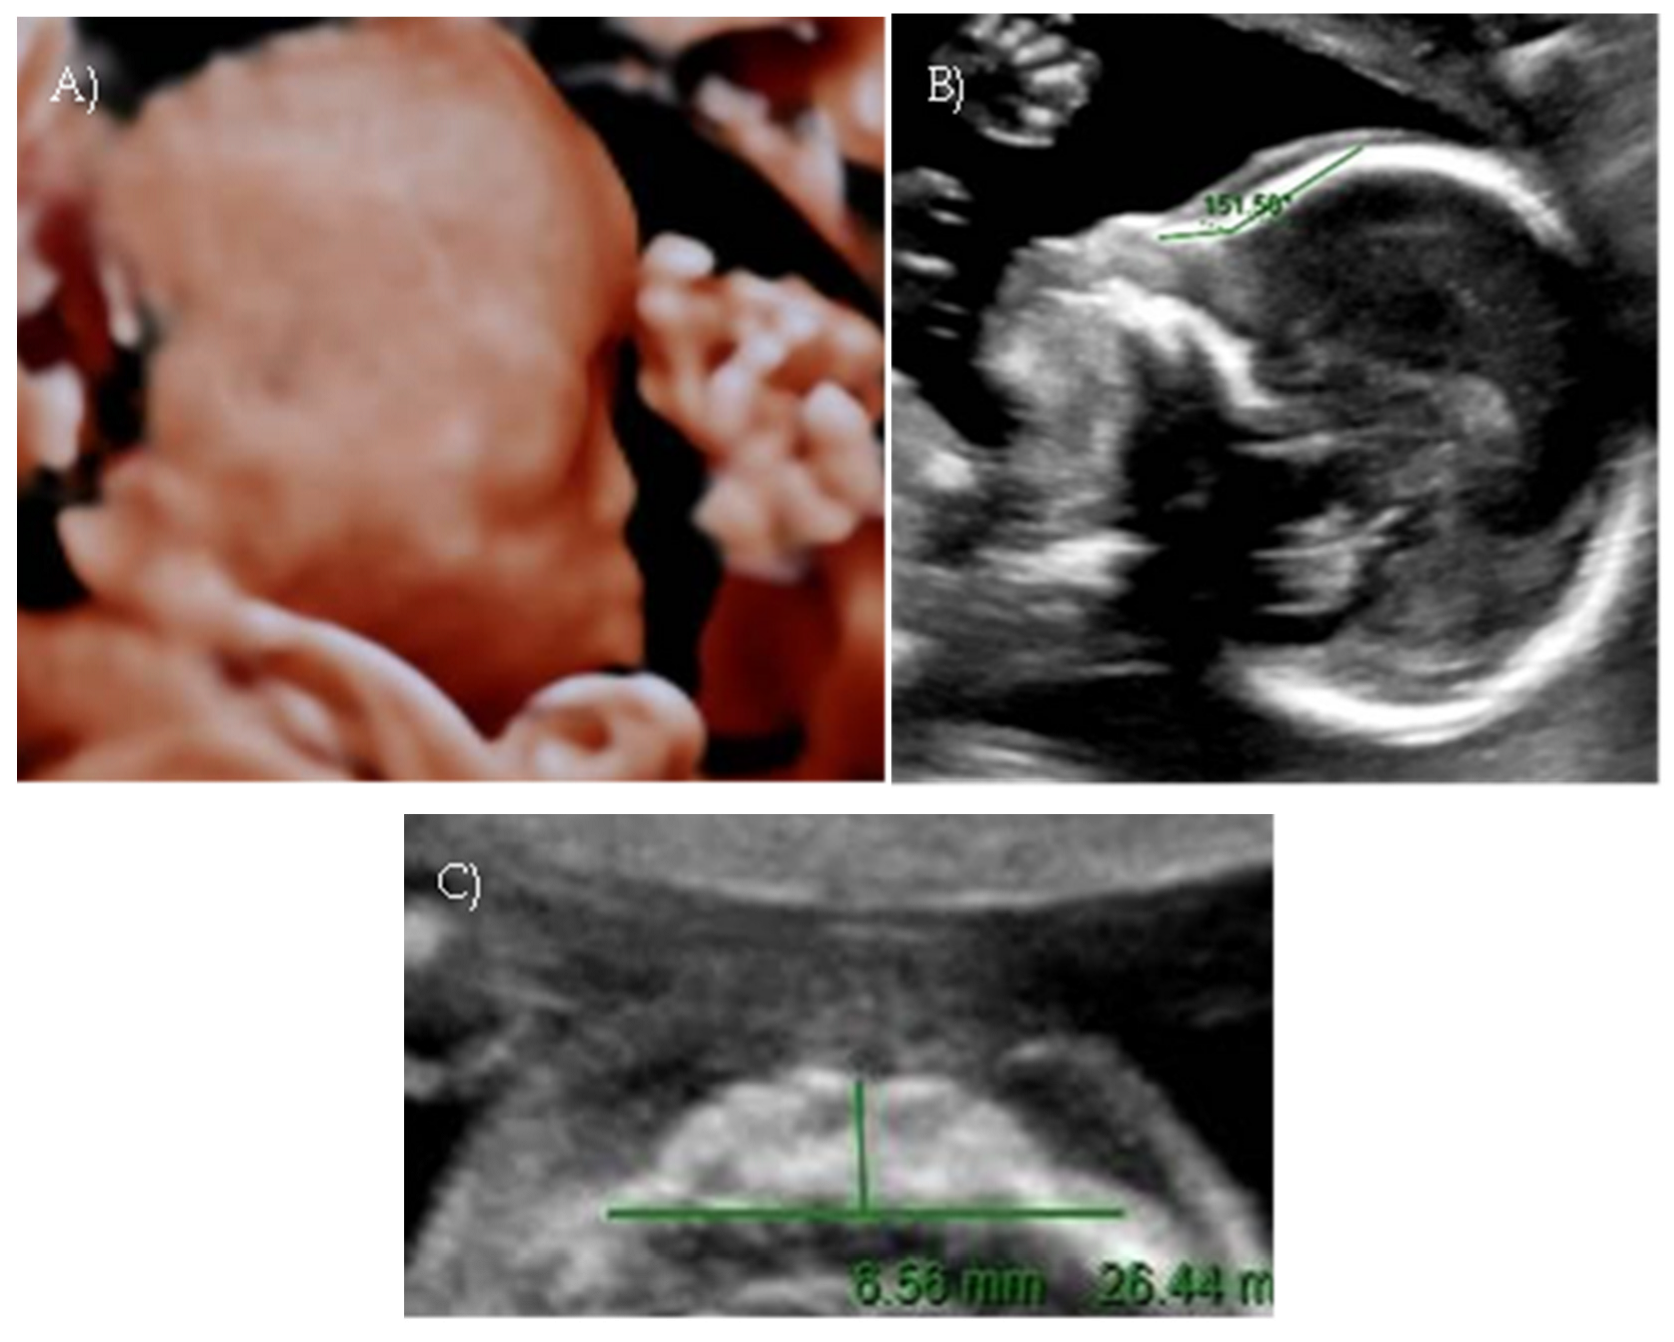

Her first-trimester combined screening for aneuploidies was low risk for trisomy 21, 18, and 13, and preterm preeclampsia. The nuchal translucency was within normal ranges (Figure 1A).

A detailed ultrasound scan was performed at 21 weeks and 1 day of gestation at our fetal medicine unit. Nasofrontal angle, nasal bone, and maxillary width were measured and compared to published references to unaffected fetuses at similar gestational ages [12,13]. Facial dysmorphism was further investigated by 3D scan (Figure 1B) through multiplanar mode and surface rendering, which allowed a more realistic representation of the fetal face, thus allowing characterization of the defect.

A flattened fetal facial profile with a nasal-frontal angle of 152.18° (cut-off: <143°, [14]), consistent with Binder-type maxillonasal dysplasia, was confirmed. To identify any other structural abnormalities, detailed examinations of the fetal anatomy and a fetal echocardiogram were conducted. No additional structural anomalies were identified (Figure 1C).

Figure 1. Case 1. (A) First-trimester 2D ultrasound Fetal profile. (B) Flat fetal profile, 21 weeks and 1 day, 3D reconstruction. (C) Nasal-frontal angle: 152.18°.